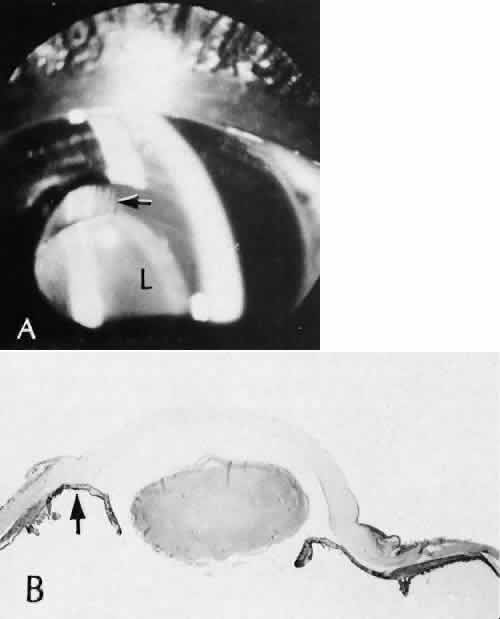

Fig. 26. Complications related to a limbal wound. A. The posterior edges of the limbal wound are poorly apposed. Incarcerated vitreous can be identified in the wound at higher magnification, (inset). The cut edges of Descemet's membrane are widely displaced (d). (Hematoxylin-eosin stain; A, × 54; inset, × 101.) B. Vitreous is incarcerated into the wound immediately anterior to an area of total anterior synechiae. C. At higher magnification, vitreous can be clearly identified in the wound. A fibrous membrane is present posterior to Descemet's membrane. The arrows indicate the cut edges of Descemet's membrane. (Periodic acid/Schiff stain; B, × 16; C, × 40.)